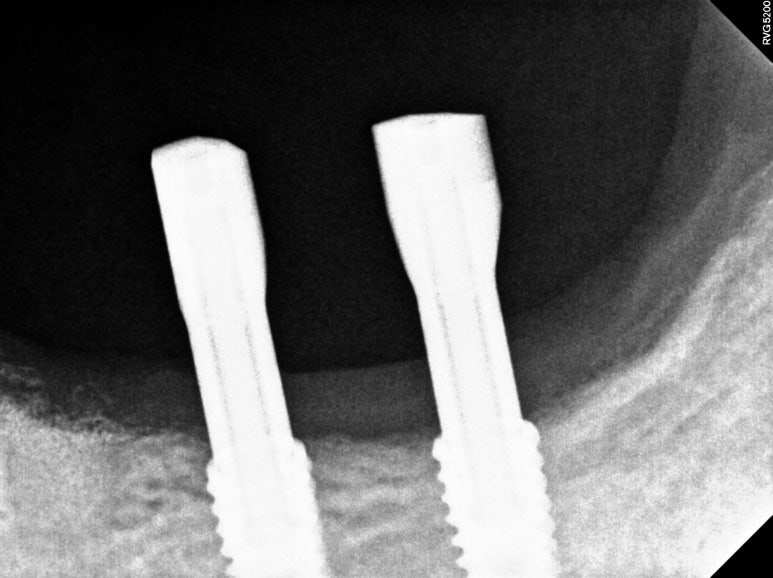

마무리는 갈끔한 엑스레이 사진으로 !!!

왼쪽 아래 어금니의 임플란트 보철물을 모두 만들고 나서의 임상 사진입니다.

자세히 보시면, 맨 뒤 어금니의 바깥쪽으로 단단하게 보이는 부착치은 (각화치은)이 잘 생착되어 있는 것을 보실 수 있어요!!

비록 많은 양은 아닙니다만,

이 최소한의 2-3mm 폭의 단단한 잇몸은

편하게 양치질을 하게 해주고, 임플란트 주변에 음식물이 끼는 것을 최대한으로 막아준답니다.

그래서 임플란트 주위염의 발생 가능성을 현저히 낮추고, 결과적으로 어금니 임플란트를 오래 쓸 수 있게 해주죠.

치료 완료 후 단단한 잇몸과 볼점막의 경계인 MGJ를 화살표로 표시해 보았는데요,

제가 유리치은이식술을 하면서 지르코니아 임플란트 크라운을 제작해드렸던 부분은

이식해놓은 단단한 잇몸이 아주 깔끔하게 자리잡으며 최적의 컨디션을 보여주고 있습니다.